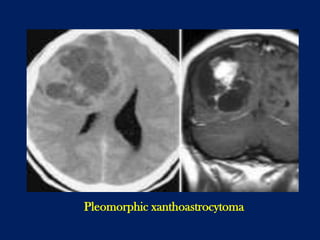

Pleomorphic xanthoastrocytoma